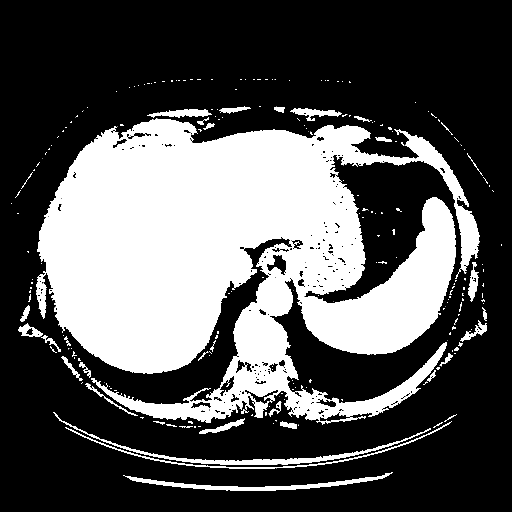

Reconstructed NATIVE CT scan (cycle consistency)

Full window (WL 1023.5, WW 4095 β†’ Low βˆ’1024, High +3071)

Actual HU range: [-1024.0, 3071.0]